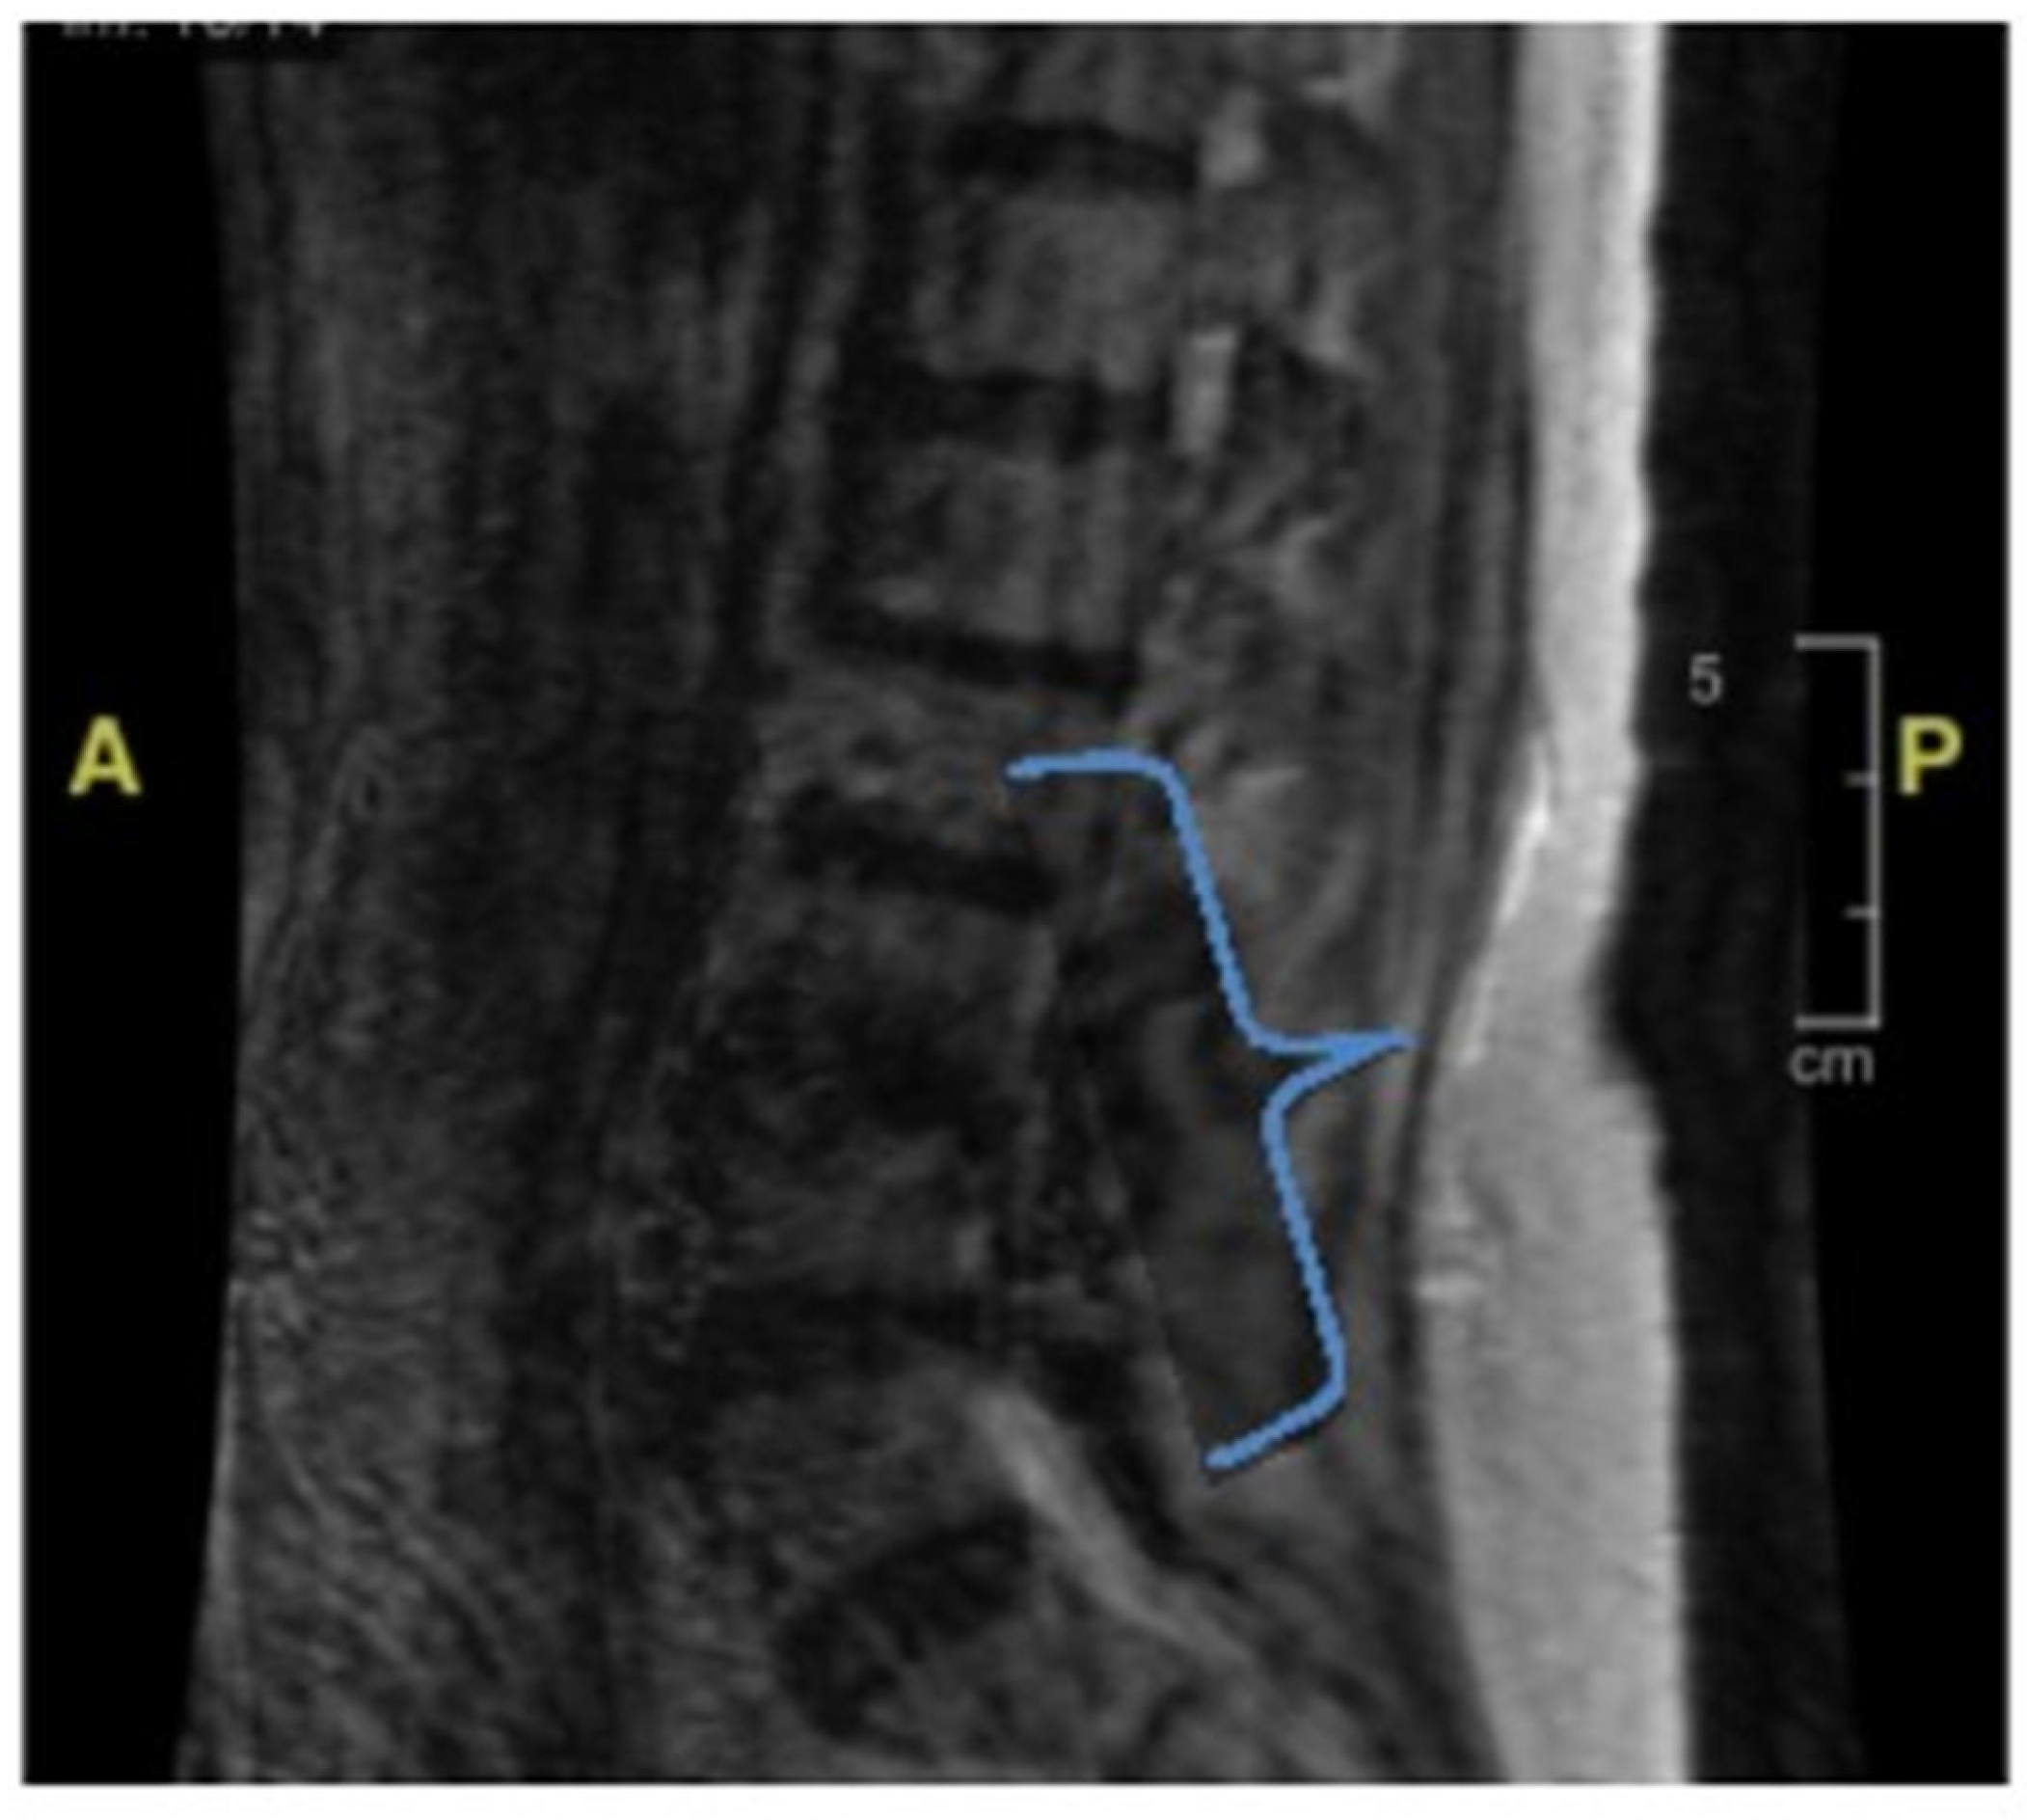

During the initial hospitalization, she was also evaluated for seven days of diplopia. She had both vertical and horizontal diplopia with mild vertiginous symptoms. Her physical examination then was remarkable for mild right-eye ptosis, subjective diplopia, left-sided facial weakness (left-sided facial droop), and decreased right hemi-body sensation to light touch associated with right lower-extremity weakness. Laboratory studies were non-diagnostic, including thyroid hormone function, vitamin B12, folate, inflammatory markers, and creatine phosphokinase. Radiological imaging, including a cerebral computed tomography scan and magnetic resonance imaging (MRI), showed no acute findings (Figure 1). She was discharged home with ophthalmologist follow-up, and the latter evaluation found no abnormality explaining her symptoms.

Figure 1. Brain magnetic resonance imaging (MRI). There is no mass effect, hemorrhage, edema, midline shift, or extra cerebral fluid collection. The ventricles and subarachnoid spaces are appropriate in size for the patient’s age.